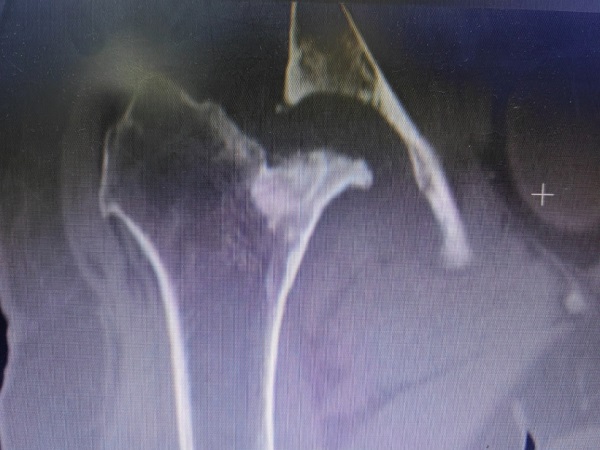

李师傅病程长,情况复杂,检查发现其骨盆倾斜,股骨头、颈部分缺如,髋臼严重骨缺损,髋关节半脱位,患肢短缩近6cm,髋关节周围软组织挛缩。手术难度大,髋部股神经、坐骨神经以及股动脉牵张损伤的风险很大,创伤骨科郭永良主任和王争刚主任医师经过充分术前讨论,制定出了细密的个性化手术方案,并与患者及家属充分交流和沟通。